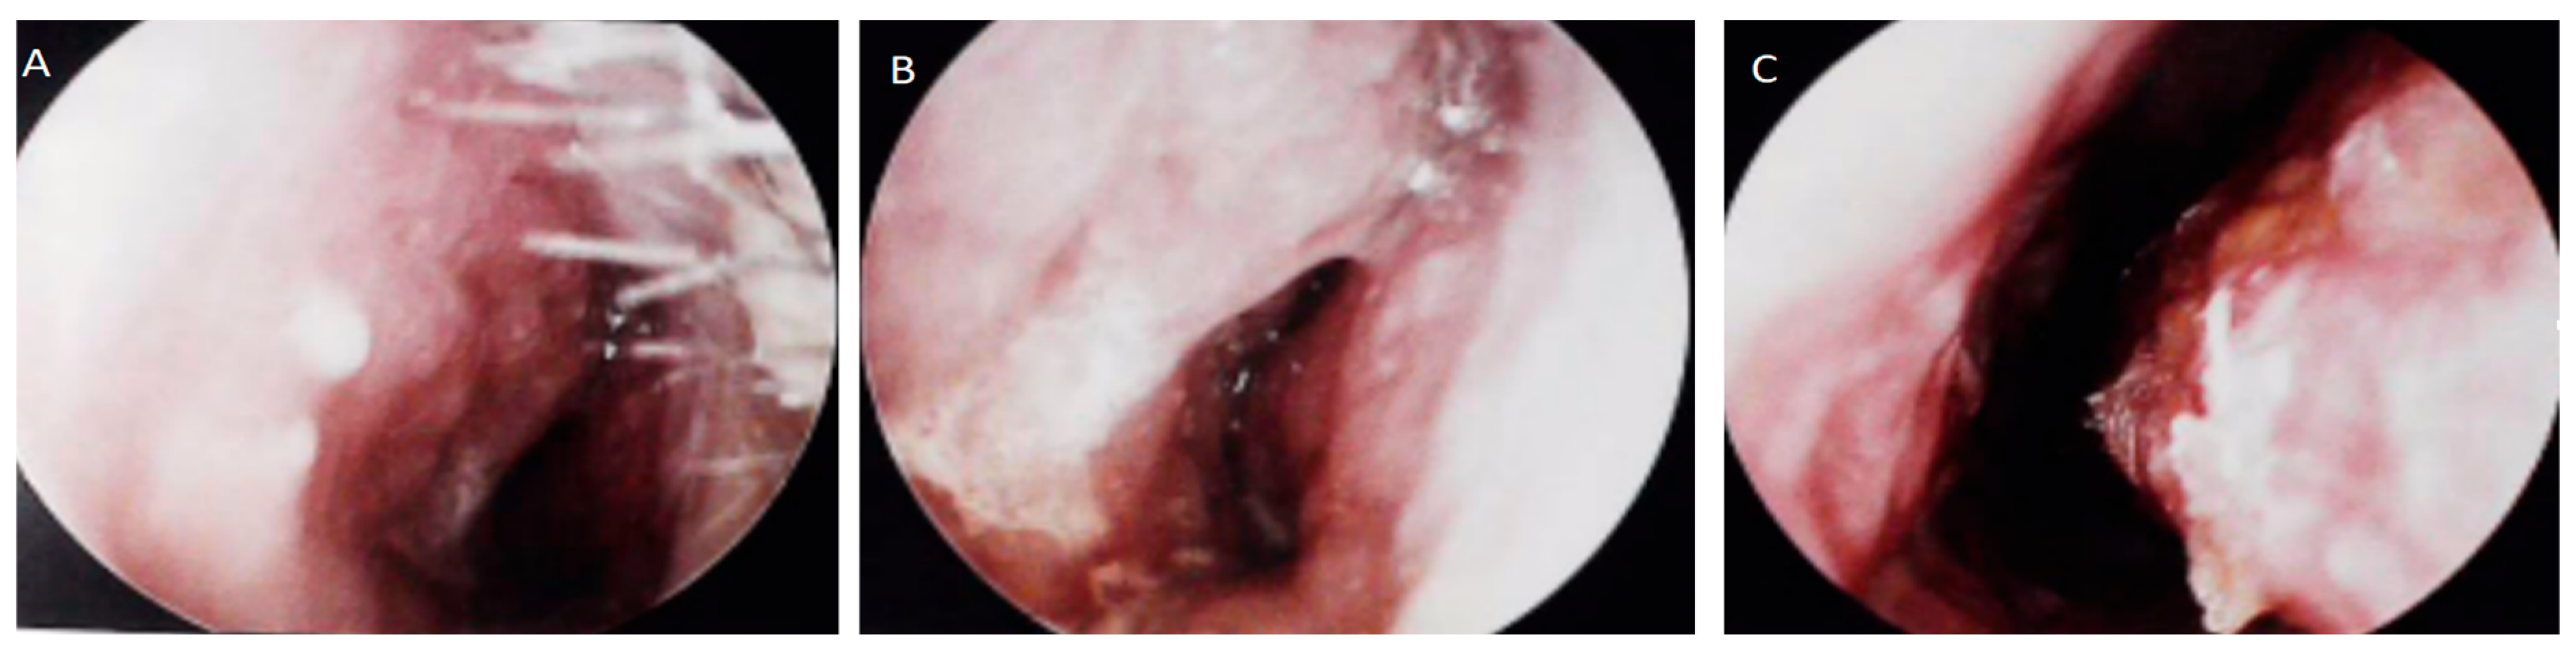

2. Report of a Case